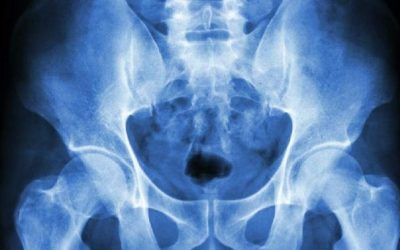

Osteopatía del pubis